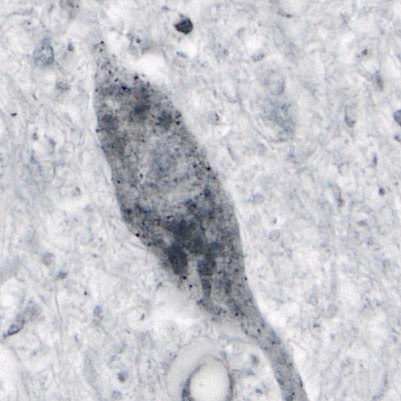

Abnormal SOD1 protein detected in human spinal cord tissue (dark spots) Trist et al. 2022.

Normally, the protein superoxide dismutase 1 (SOD1) protects cells, but a mutation in its gene is thought to make the protein ‘toxic’; this toxic protein form is associated with hereditary forms of ALS. Abnormal mutant SOD1 is only found in regions of the spinal cord where nerve cells die, implicating this abnormal protein in cell death.